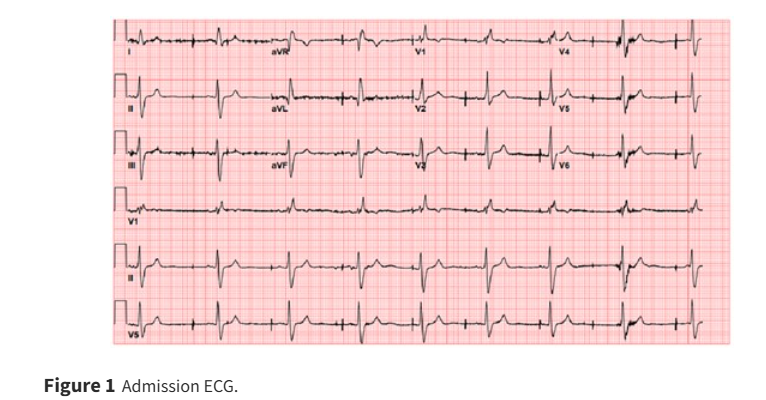

74/M p/w syncope. He had SA nodal dysfunction w DDDR PPM 10 yrs ago. What is the abnormality & cause? ow.ly/BzAP50VLVZN #EHJCaseReports Philipp Sommer Tee Joo YEO Aaysha Cader Boldizsar Kovacs Erik Rafflenbeul A.Nazmi Calik Obayda Azizy Sara Moscatelli EHJCaseReports Editor-in-Chief #CardioX #EPeeps